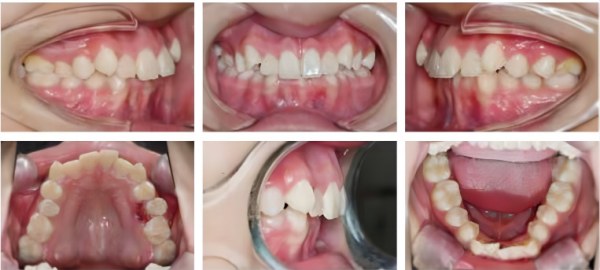

治療前

口腔内写真

矢状平面の問題: クラスIIの不正咬合、深いオーバーバイト。

垂直平面の問題: 前歯の深いオーバーバイト。

水平面の問題: 顎歯列弓は中央部で幅が広すぎますが、下顎歯列弓は狭いです。

歯科用アーチの問題: 混雑したへこみアルアーチ、左側の小臼歯の両側のはさみの咬傷。